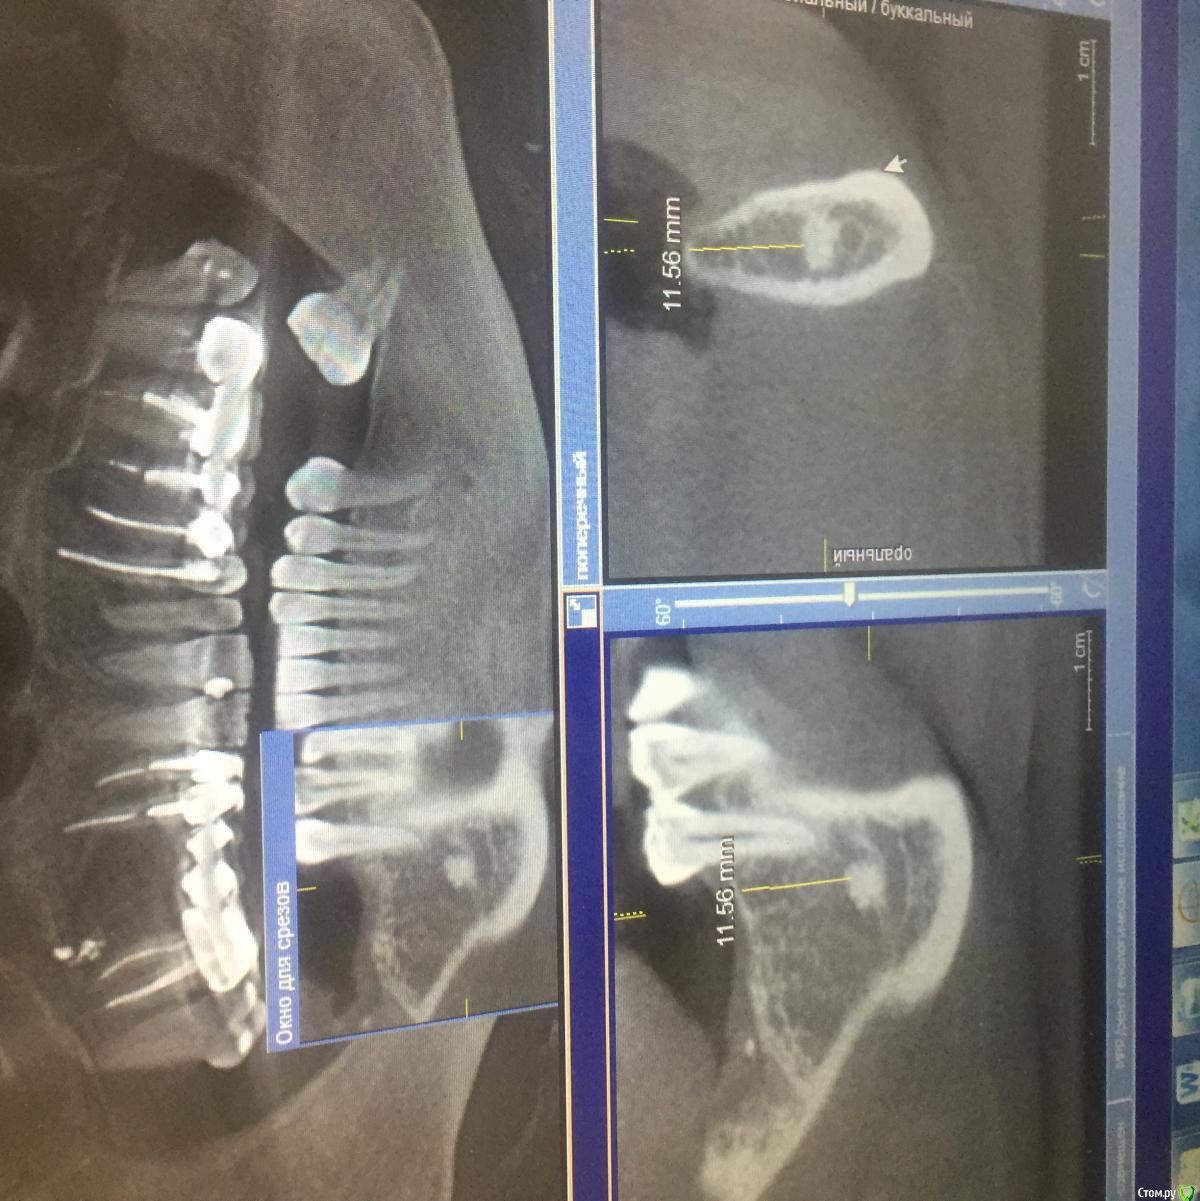

pavlin Опубликовано 27 июня, 2017 Поделиться Опубликовано 27 июня, 2017 Решили ставить имплант в обл 46. Зуб удалялся более 15 лет назад. После снимка обнаружили в обл 46 новообразование костного типа. Коллеги нужен совет. Можно ли в данном случае ставить Имплант? Образование 4,5*3мм, до него 11,5 мм. Ставить 10мм Имплант? Или ставить рядом? Или выбрать другую методику восстановления зубного ряда? Заранее благодарю Ссылка на комментарий

АнтонТЛТ Опубликовано 27 июня, 2017 Поделиться Опубликовано 27 июня, 2017 Можно хоть 10мм, хоть прям в остеому 1 Ссылка на комментарий

Aquarius Опубликовано 28 июня, 2017 Поделиться Опубликовано 28 июня, 2017 А что с шириной гребня ? по остеоме - хоть в нее, хоть не доходя до нее. Ссылка на комментарий

pavlin Опубликовано 28 июня, 2017 Автор Поделиться Опубликовано 28 июня, 2017 А что с шириной гребня ? по остеоме - хоть в нее, хоть не доходя до нее. По ширине 3,5мм будем делать одномоментно с графтом и мембраной. Просто испугался новообразования , коллега сказал , что это противопоказание к имплантации, вот и возник вопрос Ссылка на комментарий

kamranchick Опубликовано 5 июля, 2017 Поделиться Опубликовано 5 июля, 2017 думаю при таком расположении имплантата, в области крестального модуля ширина гребня я думаю около 5мм будет... Ссылка на комментарий

surf Опубликовано 6 июля, 2017 Поделиться Опубликовано 6 июля, 2017 Доктор планирует имплантацию с аугментацией( показания налицо) Видимо,имеет навыки( хотя не точно), пациент,предположительно,готов финансово,раз имеется план(тоже не факт, но все же)Отсюда вопрос,к чему все эти советы про заглубить и срезать?!к чему здесь эти компромиссы?!Почему говорят,что так лучше?!!Доктор! Делайте как решили, можно даже чуть отступить от пятерки,слишком уж Вы близко к ней мерить начали раз уж шестерку ставим,так если хотите и подлинней поставите и остеому обойдёте( что не обязательно) с лёгким мезио-дистальным наклоном.ИМХО. Ссылка на комментарий